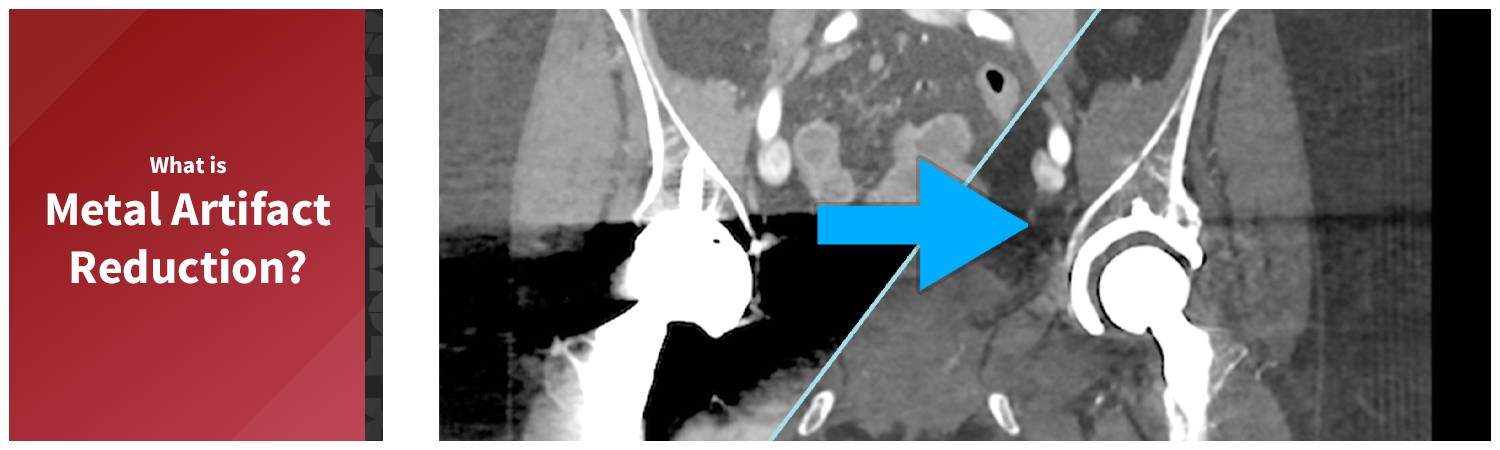

Figure B: Coronal view of a CT scan with significant metal artifact distortion around the pelvis due to hip replacement hardware.

Figure C: The same coronal imaging from figure B, after metal artifact reduction algorithms have been applied.